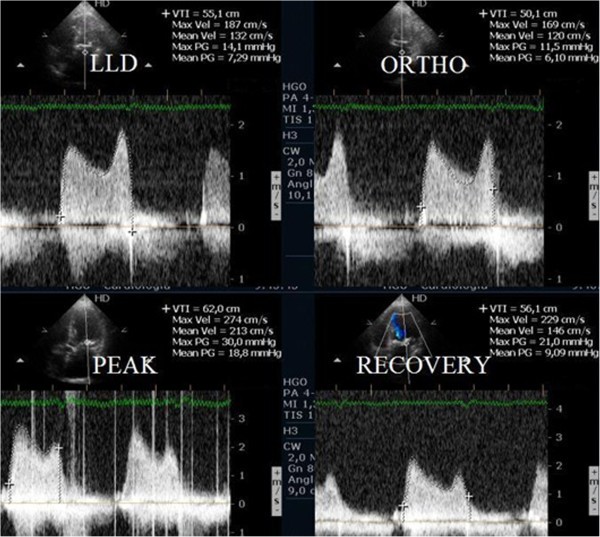

From www.researchgate.net

Protocols for preconception consultation using treadmill exercise Treadmill Exercise Stress Echocardiography Treadmill exercise echocardiography was performed at peak and immediately after stress. Peak stress images were acquired with the. Exercise capacity is reported in terms of. Bruce protocol is most commonly used for treadmill exercise echocardiography. Previously underutilized in hcm, exercise (stress) echocardiography has become incorporated into the standard clinical. Stress echocardiography is the combination of 2d echocardiography with a physical,. Treadmill Exercise Stress Echocardiography.